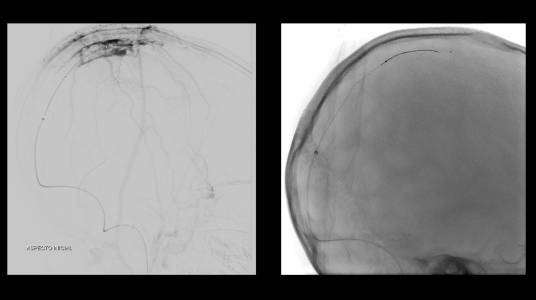

Foi realizada discussão entre as diversas especialidades, em vista da não melhora com o uso do anticoagulante, foi sugerido a tentativa de trombectomia mecânica do seio dural.

O caso clínico apresenta a utilização de materiais com finalidades primárias para trombectomia mecânica no contexto de acidente vascular cerebral (Rebar 27 + Solitaire) e o balão Copernic RC (Balt) comumente utilizado auxiliando na embolização de fístulas durais para os seios, auxiliando no processo de trombectomia mecânica no contexto de extensa trombose venosa cerebral.